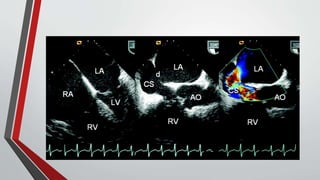

Echocardiography

• The functional importance of the defect can be estimated by the size of the right ventricle,

• The presence or absence of right ventricular volume overload (paradoxical septal motion),

• (less accurately) estimation of Qp/Qs.

• Indirect measurement of pulmonary artery pressure can be obtained from the Doppler velocity of the tricuspid

regurgitation jet.

• In ostium secundum atrial septal defects, : The mitral valve abnormalities consist of thickening and fibrosis of leaflets and

chordae tendineae .

• TEE permits better visualization of the interatrial septum and is usually required when device closure is contemplated,

partly to ensure that pulmonary venous drainage is normal

• ICE can be used instead of TEE during device closure to help guide insertion of the device, thereby reducing fluoroscopic

and procedural time and forgoing the need for general anesthesia.